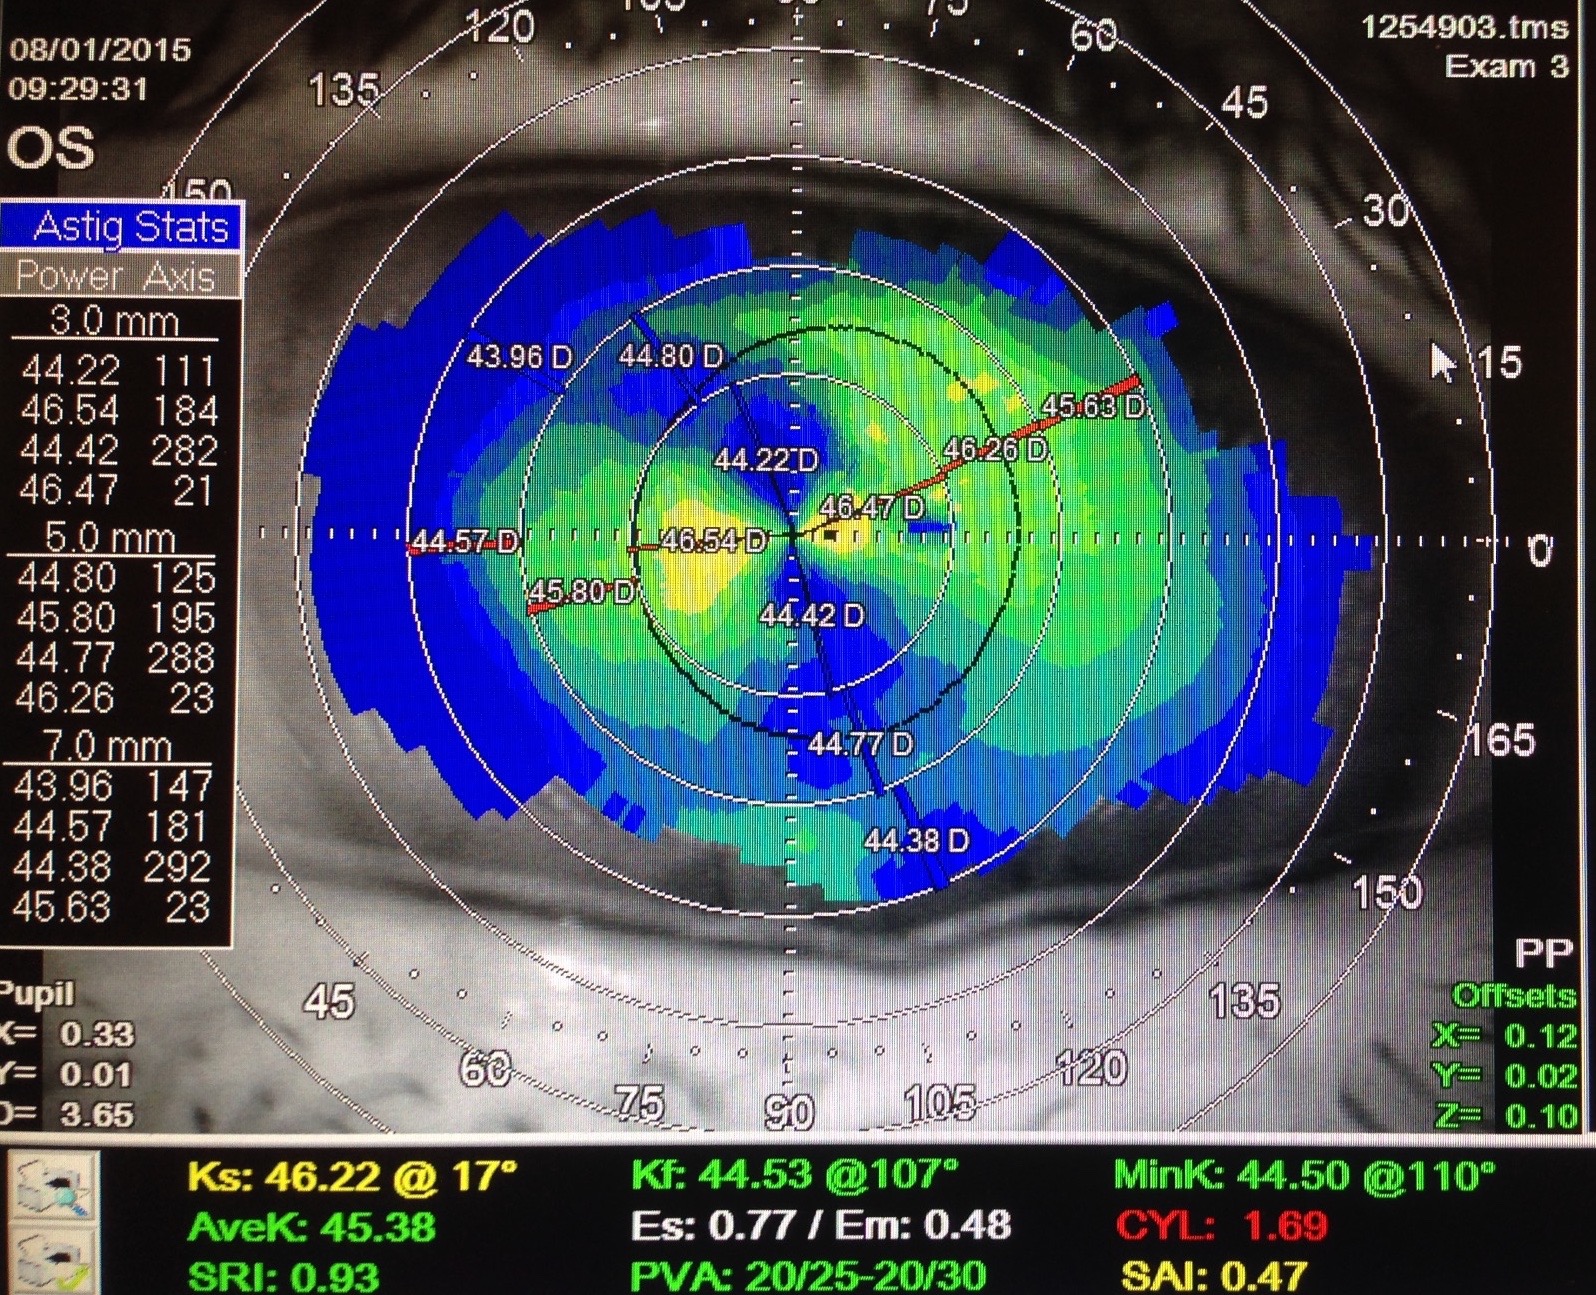

Topographie cornéenne : kératocone, astigmatisme irrégulier